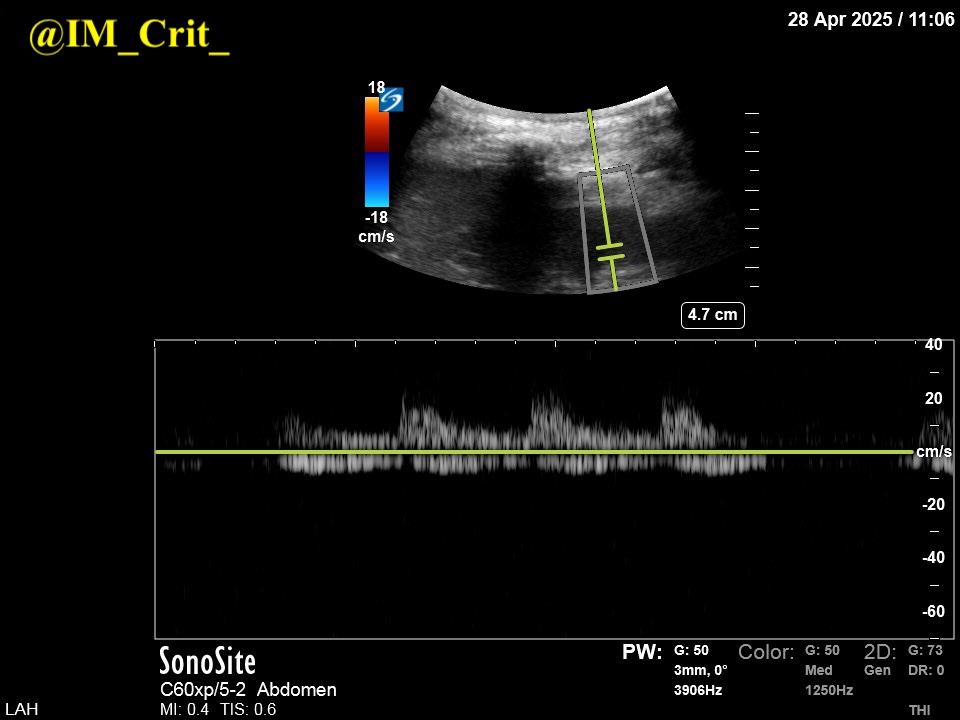

I did POCUS: hyperdynamic LV, no pericardial effusion, RV OK, IVC very small (images not shown). I threw some color Doppler in the LV and this happened:

"A lot of color"! -> high velocity signals in the LV cavity and probably the LVOT. US windows not good (pt on the vent; subcostal views impossible given recent laparotomy), so I tried some continuous Doppler in the LVOT:

☝️Voila! A dagger-shaped signal with max velocity of 6 m/sec. I was not interested in finding exactly where the obstruction was. I bolused ivf, started vasopressin 0.04 and gave 5 mg iv metoprolol. In a few hours, lactate was normal and levo was ⬇️by 2/3.

Patient seemed to benefit from being managed as one with LV outflow tract obstruction. I would have never tried iv metoprolol in a pt on industrial doses of pressors. In the past, I might have tried esmolol that can be dc/ed fast. POCUS makes us smarter at the bedside. To be fair